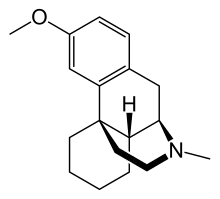

The pharmacodynamic response to an opioid depends upon the receptor to which it binds, its affinity for that receptor, and whether the opioid is an agonist or an antagonist. For example, the supraspinal analgesic properties of the opioid agonist morphine are mediated by activation of the μ1 receptor; respiratory depression and physical dependence by the μ2 receptor; and sedation and spinal analgesia by the κ receptor. Each group of opioid receptors elicits a distinct set of neurological responses, with the receptor subtypes (such as μ1 and μ2 for example) providing even more [measurably] specific responses. Unique to each opioid is its distinct binding affinity to the various classes of opioid receptors (e.g. the μ, κ, and δ opioid receptors are activated at different magnitudes according to the specific receptor binding affinities of the opioid). For example, the opiate alkaloid morphine exhibits high-affinity binding to the μ-opioid receptor, while ketazocine exhibits high affinity to ĸ receptors. It is this combinatorial mechanism that allows for such a wide class of opioids and molecular designs to exist, each with its own unique effect profile. Their individual molecular structure is also responsible for their different duration of action, whereby metabolic breakdown (such as N-dealkylation) is responsible for opioid metabolism.

Dextromethorphan (the stereoisomer of levomethorphan, a semi-synthetic opioid agonist) and its metabolite dextrorphan have no opioid analgesic effect at all despite their structural similarity to other opioids; instead they are potent NMDA antagonists and sigma 1 and 2-receptor agonists and are used in many over-the-counter cough suppressants.